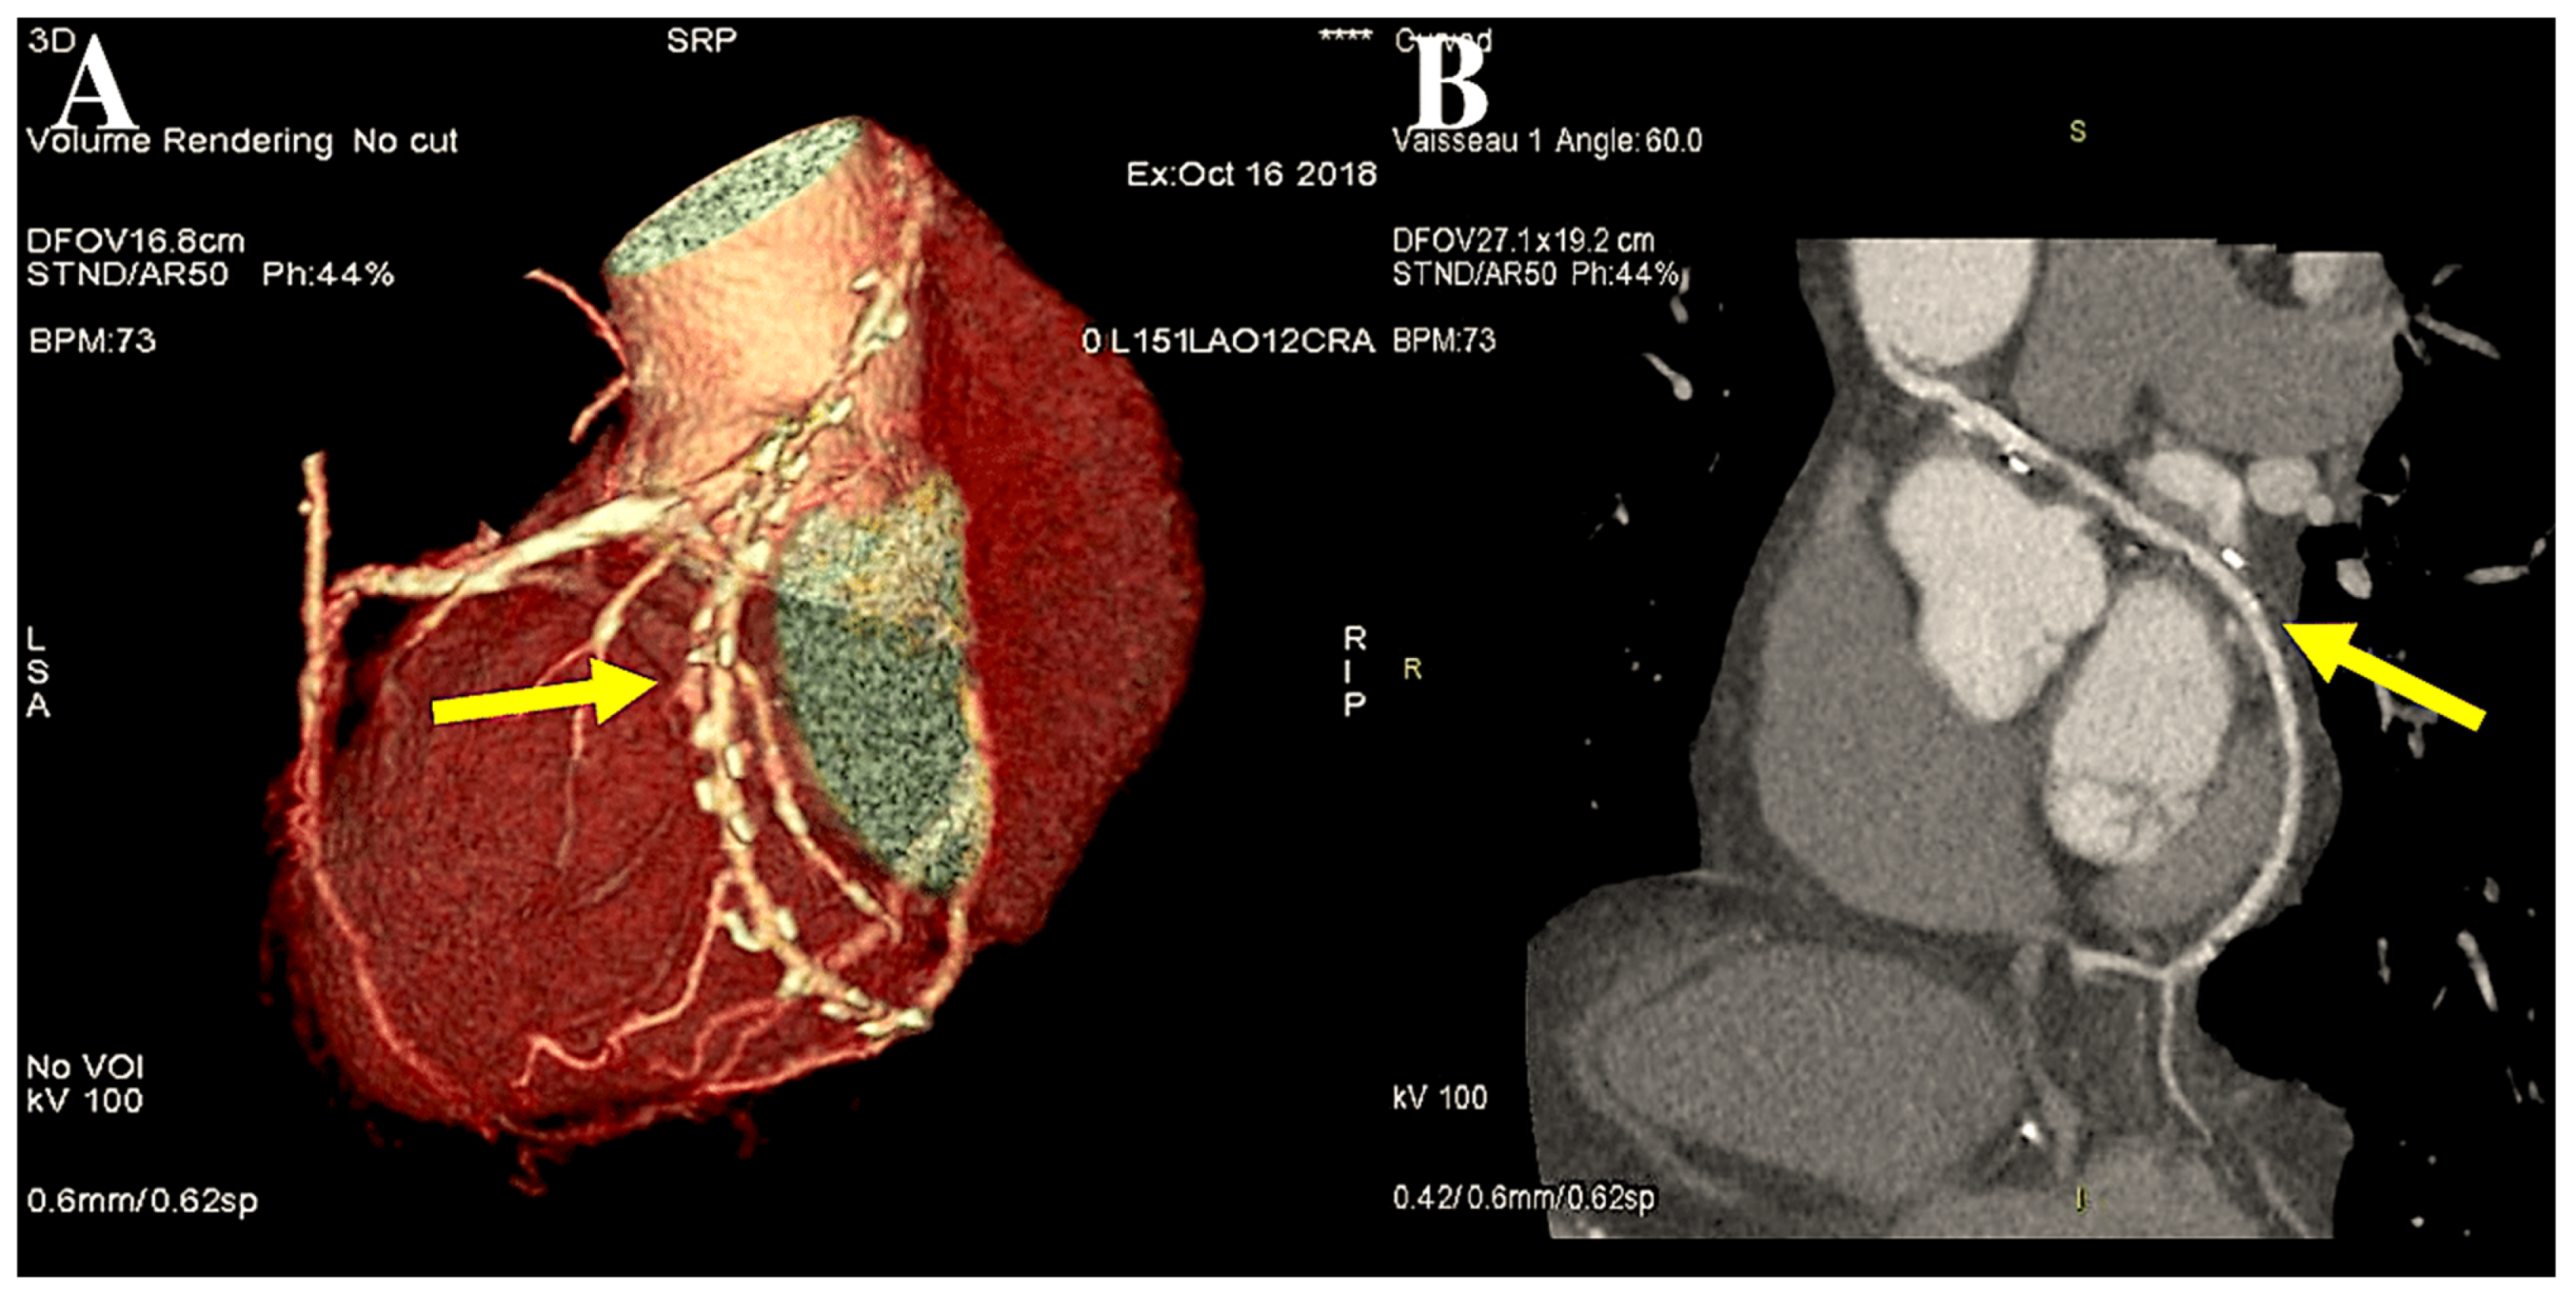

6. The Destiny of Radial Artery Grafts

Determinants of RA Patency